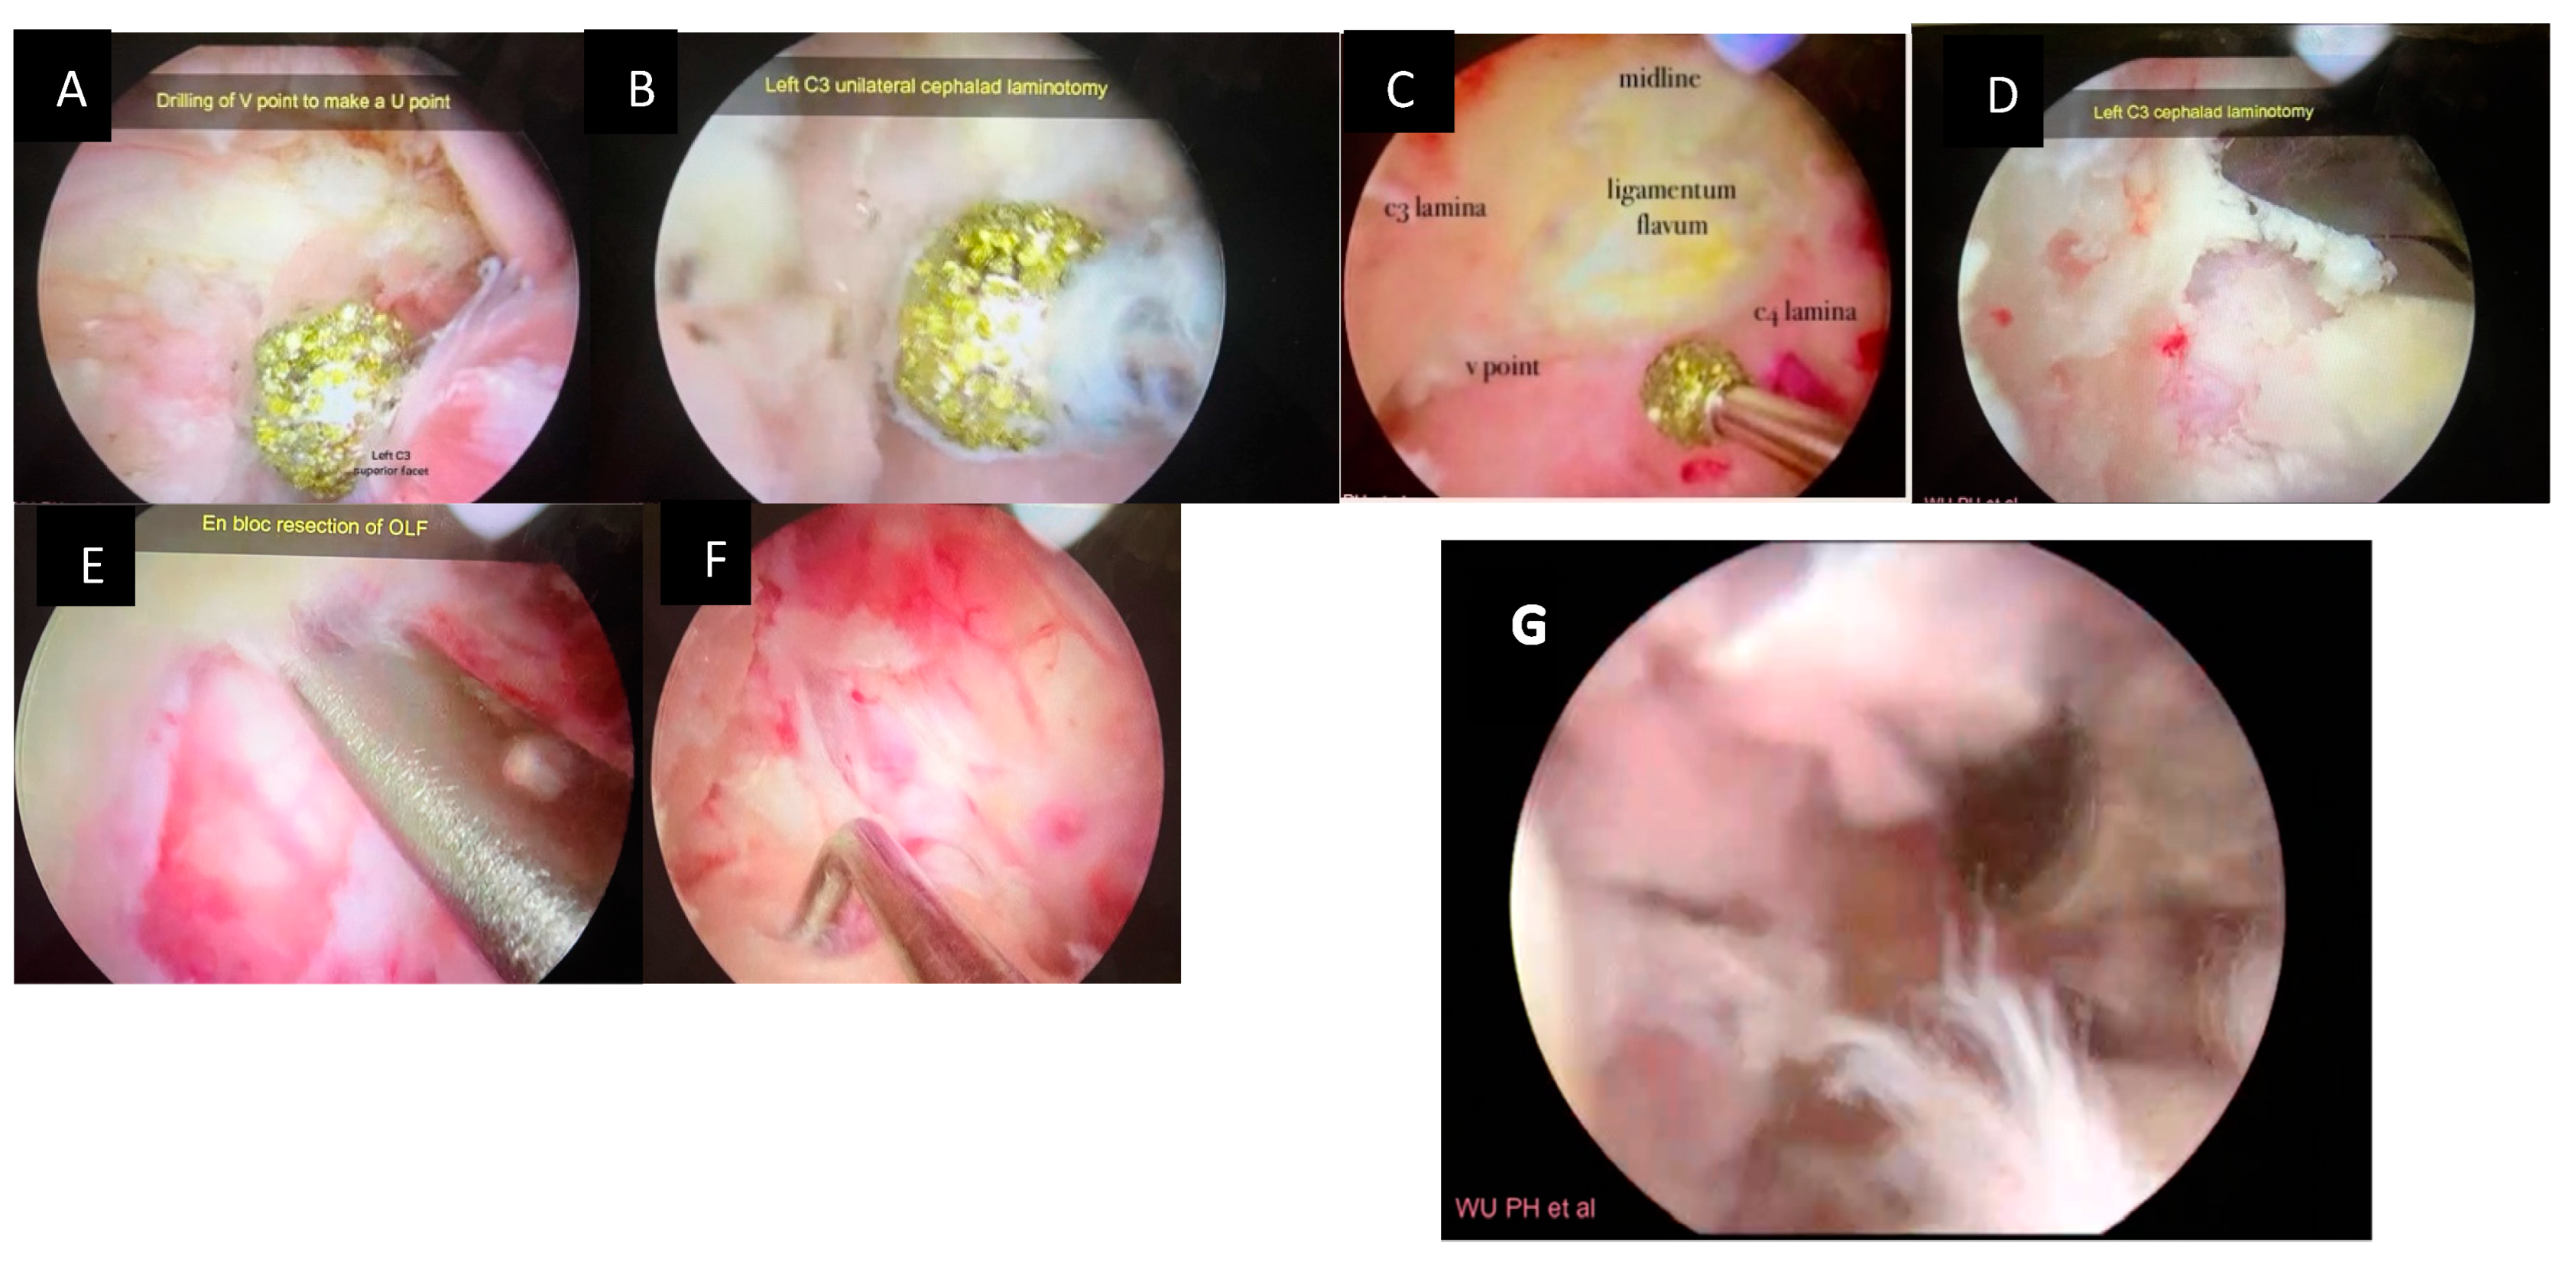

The upper lamina (C3) is drilled starting at the inferolateral region, then proceeding in the craniolateral direction with the 3.0 mm spherical diamond burr. This is done until the ligament flavum is just detached from the upper lamina. The superolateral part of the lower lamina (C4) is then burred in the caudal direction until it is paper thin. The ligament flavum should be preserved until the bone work is finished for the protection of the thecal sac (Figure 4A–C).

Figure 4.

Intraoperative pictures showing various stages of posterior decompression and flavectomy. (A): Drilling at the V point, (B): drilling of cephalad lamina until the margin of OLF, (C): drilling until the caudal margin of OLF, (D): cephalad laminotomy with a 1 mm Kerrison punch (E): lifting and en bloc removal of OLF by a fine dissector, (F): dura after resection of ligamentum flavum, (G): video of the UBE_technique (Video S1).

The sublaminar area of the contralateral side is drilled until the medial part of the contralateral facet is exposed. This is carried out while retaining the spinous process and the contralateral outer cortical bone (Figure 3E–G). Further, the thinned area of the lamina is removed using the fine dissector or 1 mm Kerrison punch (Figure 4D)

2.8. Detaching the Ligamentum Flavum en Bloc

Subsequently, the LF is separated from the edges of attachment to the lamina and the facet joints using a fine dissector and nerve hook (Figure 4E). Then, the LF is removed en bloc (Figure 5B) using fine pituitary forceps, and the dura is fully exposed. (Figure 4F).